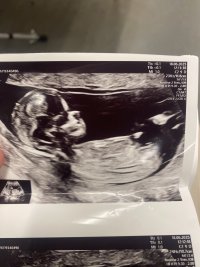

Syns dette ser veldig ut som en gutt, pga det «laget» oppå + at den går oppover. Men har du noen flere bilder?13+2 noen som har en tanke her? Synst selv nubben her er mye flatere enn med gutten jeg har

Usikker på om det er nub man ser?13+2 noen som har en tanke her? Synst selv nubben her er mye flatere enn med gutten jeg har

Har disse, men tror ikke nub viser herSyns dette ser veldig ut som en gutt, pga det «laget» oppå + at den går oppover. Men har du noen flere bilder?![]()

Jeg spurte flere sider, men ene sa at de ikke ville si noe da bare en liten del av Nuben visste så det var vanskelig å si noe om kjønn..Usikker på om det er nub man ser?